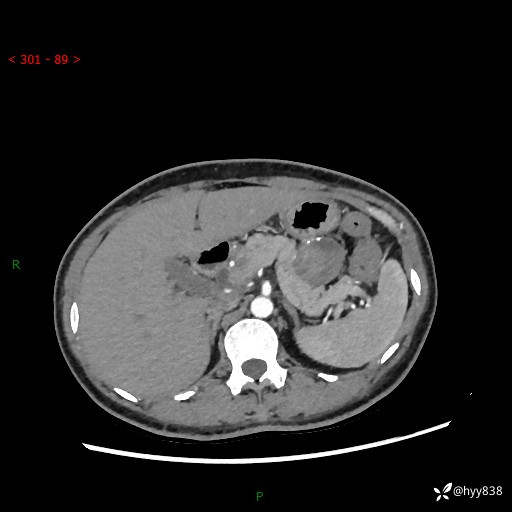

胰腺CT平扫

增强动脉期+静脉期